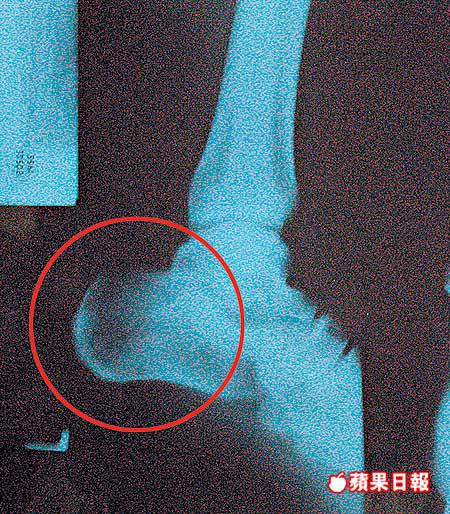

明愛醫院函覆,李大衛左足踝受傷後到該院求診,經X光、骨掃描及其他測試並無骨折,後因他感左足踝疼痛及不穩定,骨科醫生遂安排他接受手術,事前已說明手術後可能有足踝繃緊情況,並經其簽署同意書始進行手術。手術中用作固定鬆弛韌帶的金屬釘,乃骨科常用物料,通常不會引致發炎。

韌帶穩定測試正常

醫院在手術後為他安排物理治療,其後其足踝恢復活動能力,韌帶穩定測試正常,沒有感染或發炎症狀,出院後繼續在骨科專科門診覆診跟進。鑑於李先生的情況穩定,今年6月醫療判傷委員會為他判傷,評定有2%永久傷殘,並註明左足踝無繃緊。